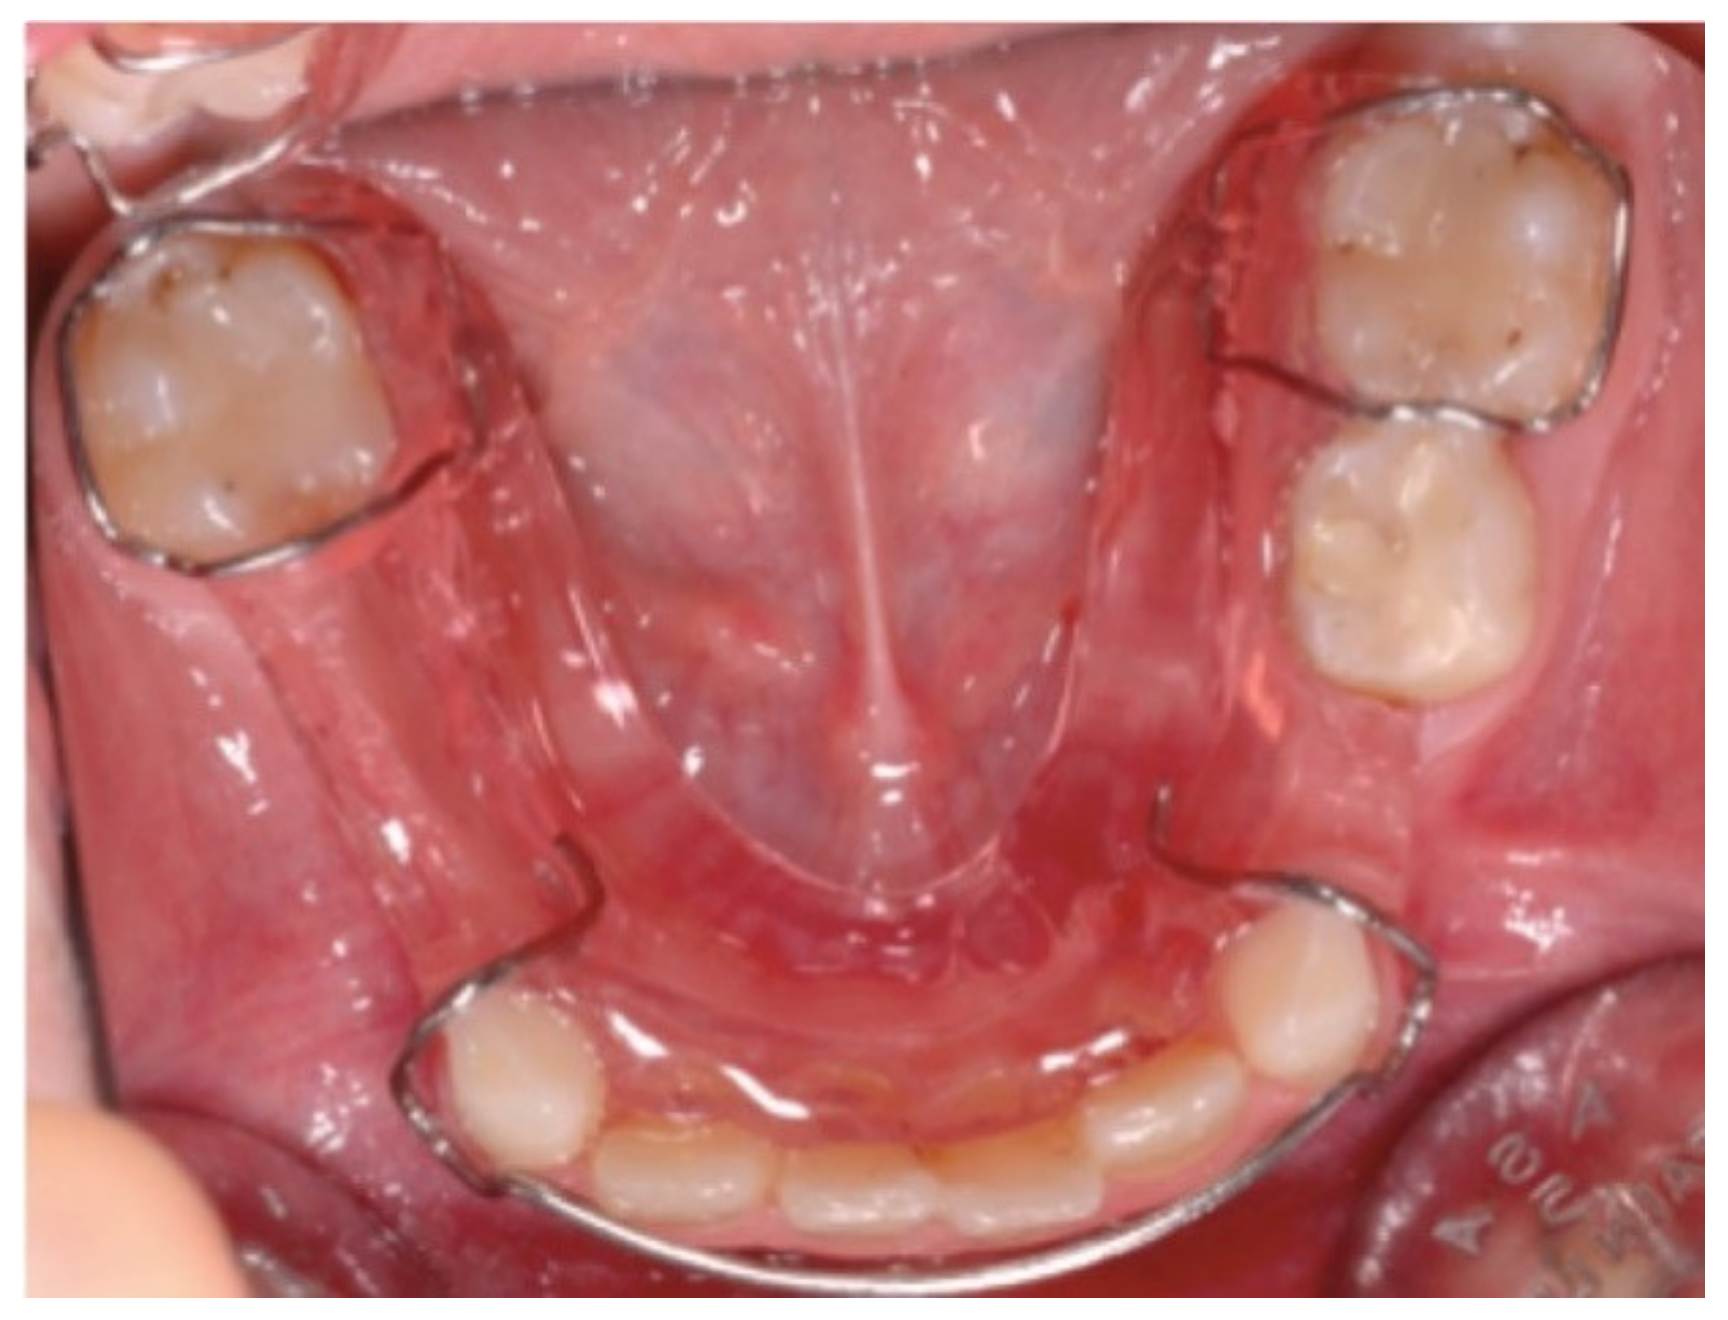

3.2. Pediatric Dentistry Specialist Management of Dental Anomalies in Children with CLP